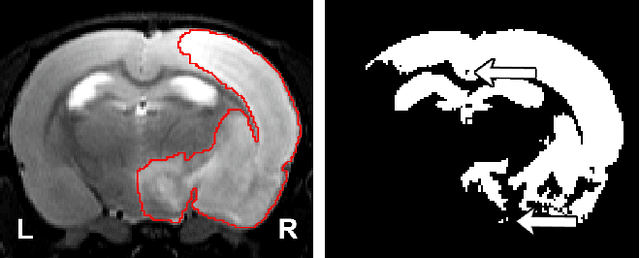

Abstract:We present MedicDeepLabv3+, a convolutional neural network that is the first completely automatic method to segment brain hemispheres in magnetic resonance (MR) images of rodents with lesions. MedicDeepLabv3+ improves the state-of-the-art DeepLabv3+ with an advanced decoder, incorporating spatial attention layers and additional skip connections that, as we show in our experiments, lead to more precise segmentations. MedicDeepLabv3+ requires no MR image preprocessing, such as bias-field correction or registration to a template, produces segmentations in less than a second, and its GPU memory requirements can be adjusted based on the available resources. Using a large dataset of 723 MR rat brain images, we evaluated our MedicDeepLabv3+, two state-of-the-art convolutional neural networks (DeepLabv3+, UNet) and three approaches that were specifically designed for skull-stripping rodent MR images (Demon, RATS and RBET). In our experiments, MedicDeepLabv3+ outperformed the other methods, yielding an average Dice coefficient of 0.952 and 0.944 in the brain and contralateral hemisphere regions. Additionally, we show that despite limiting the GPU memory and the training data to only three images, our MedicDeepLabv3+ also provided satisfactory segmentations. In conclusion, our method, publicly available at https://github.com/jmlipman/MedicDeepLabv3Plus, yielded excellent results in multiple scenarios, demonstrating its capability to reduce human workload in rodent neuroimaging studies.

Abstract:Segmentation of rodent brain lesions on magnetic resonance images (MRIs) is a time-consuming task with high inter- and intra-operator variability due to its subjective nature. We present a three-dimensional fully convolutional neural network (ConvNet) named RatLesNetv2 for segmenting rodent brain lesions. We compare its performance with other ConvNets on an unusually large and heterogeneous data set composed by 916 T2-weighted rat brain scans at nine different lesion stages. RatLesNetv2 obtained similar to higher Dice coefficients than the other ConvNets and it produced much more realistic and compact segmentations with notably less holes and lower Hausdorff distance. RatLesNetv2-derived segmentations also exceeded inter-rater agreement Dice coefficients. Additionally, we show that training on disparate ground truths leads to significantly different segmentations, and we study RatLesNetv2 generalization capability when optimizing for training sets of different sizes. RatLesNetv2 is publicly available at https://github.com/jmlipman/RatLesNetv2.